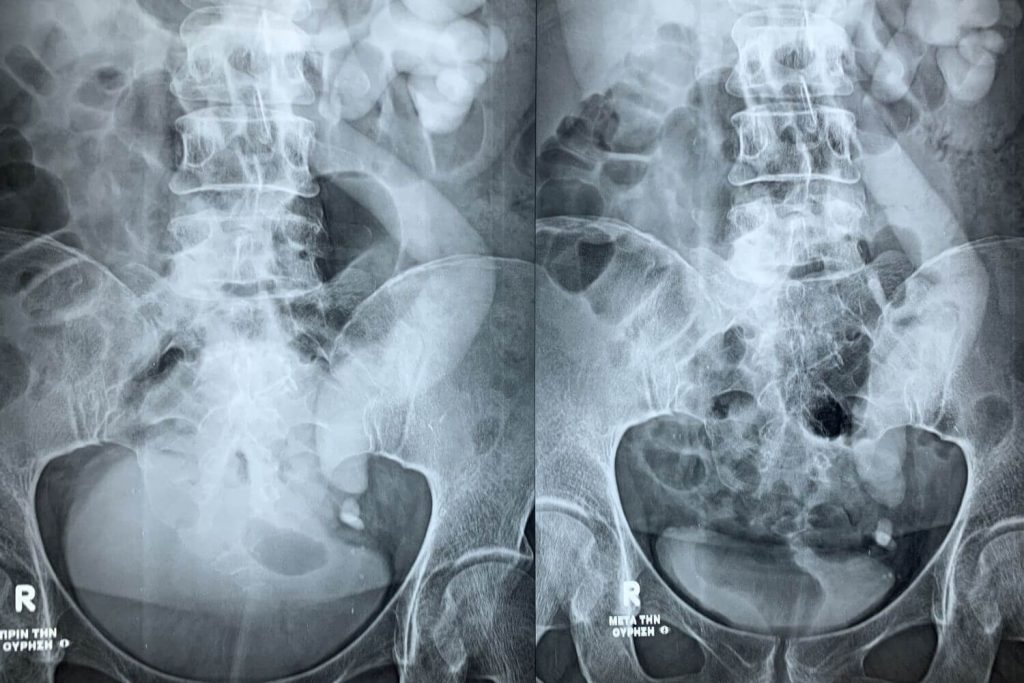

Κατόπιν έγινε ουρητηροσκόπηση και ενδοσκοπική λιθοτριψία με Laser.

Η ασθενής έλαβε εξιτήριο την ίδια ημέρα ενώ το stent αφαιρέθηκε σε 2 εβδομάδες.